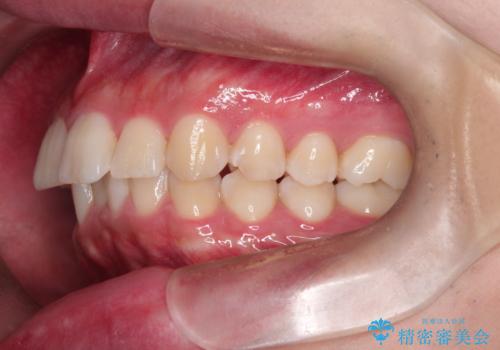

【インビザライン】短期間で出っ歯を治したい

- 出っ歯と口元の突出感が気になるということで来院されました。抜歯矯正も考えられますが、今回は早く終わらせたいという要望があり非抜歯での治療にしました。また遠方から来院されているため、来院回数のおさえられるインビザラインを選択しました。

非抜歯での治療のため、今回はスペース確保のために遠心移動とおもにIPRの処置を取り入れました。